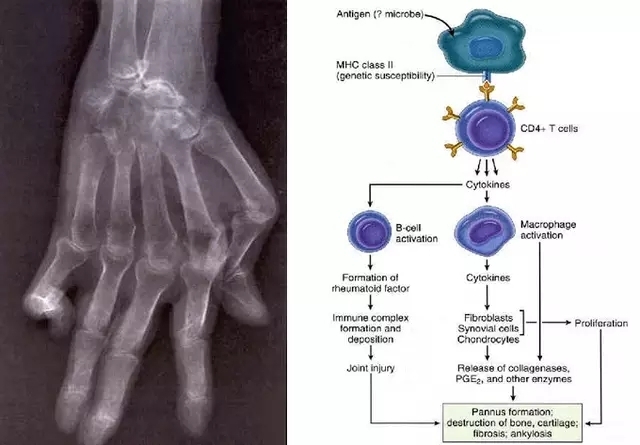

NO.2 系统性红斑狼疮(SLE)

目前认为其发生系机体免疫功能异常,进而自身抗体造成多系统、器官、组织损伤的自身免疫性疾病。其诊断主要依赖多系统受累表现(美国风湿学会推荐的SLE分类标准)及自身免疫水平异常(抗ds-DNA抗体、抗Sm抗体、抗磷脂抗体、抗核抗体等)证据。

图为系统性红斑狼疮致急性化脓性胰腺炎伴出血脓肿形成

消化系统改变:胃灼热、吞咽困难(目前认为可能与食管肌层、纵隔结缔组织受累相关)常见(50%以上),恶心、食欲下降、呕吐(50%),腹痛(20%),腹泻(5%—25%),腹膜炎、肠系膜血管炎、胰腺炎相对少见。

另有肝损伤(50%转氨酶升高、30%肝大、肝脂肪变较常见),有20%的患者可表现为脾大。